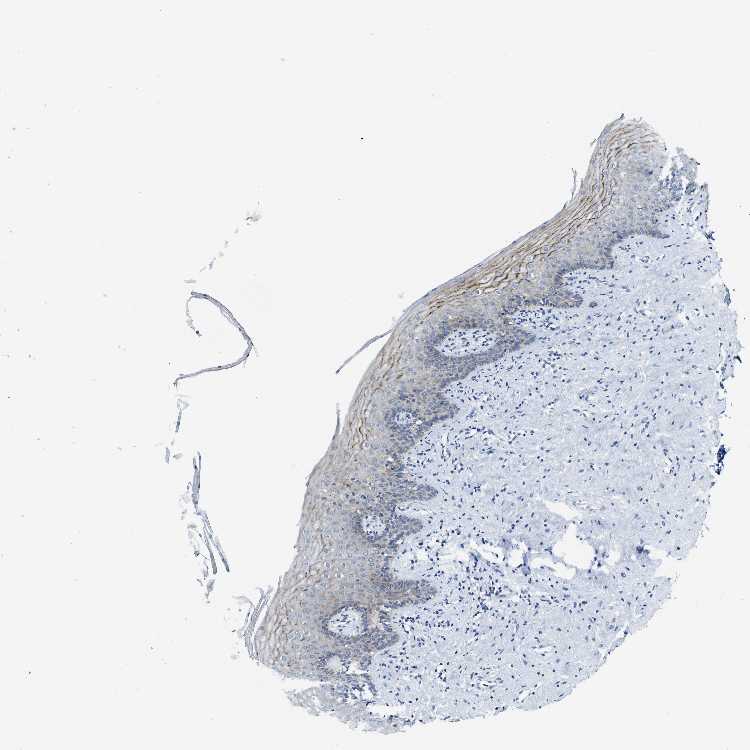

TISSUE PRIMARY DATA VAGINA Show tissue menu

VAGINA - Antibody stainingi

Antibody staining in the annotated cell types in the current human tissue is reported as not detected, low, medium, or high, based on conventional immunohistochemistry profiling in selected tissues. This score is based on the combination of the staining intensity and fraction of stained cells.

Each image is clickable and will lead to virtual microscopy that enables deeper exploration of all samples and also displays staining intensity scores, fraction scores and subcellular localization as well as patient and tissue information for each sample.

Antibody HPA018331

Squamous epithelial cells Medium